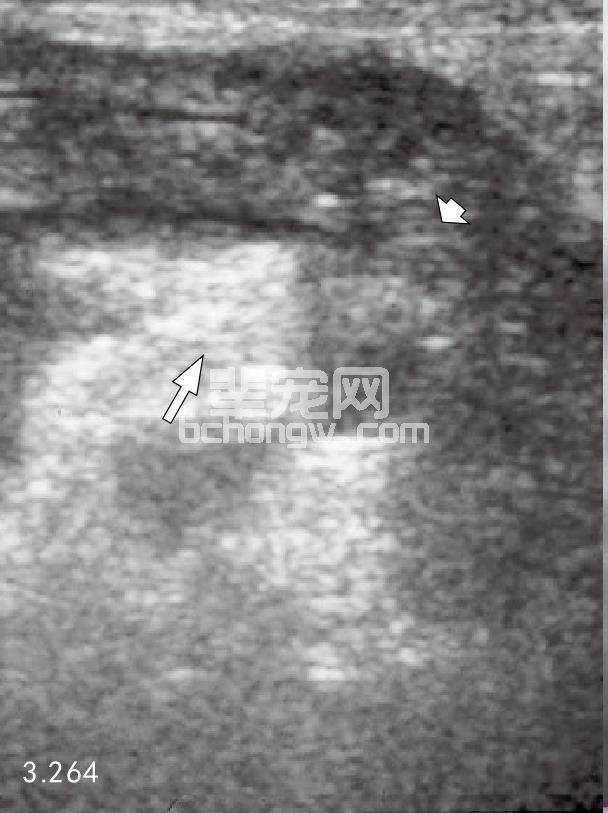

图3.264 一只7岁雄性英国可卡犬腹部超声波检查为典型的急性胰腺炎病变,包括胰腺实质的低回声(短箭头所指)和炎性胰腺周围脂肪明显的高回 声,其脂肪含有多量钙沉积(长箭头所指)。该犬也有患艾迪生病的危险。患犬无尿最后安乐死。尸体剖解发现包括急性坏死性胰腺炎(与图3.257、 图3.258相似),双侧肾上腺皮质萎缩,甲状腺萎缩。它是不能治疗的甲状腺功能减退导致了高脂血症,高脂血症导致犬急性胰腺炎。

超声波在探查与胰腺炎相关的病理变化时是很有用的。然而,正常胰腺很少显现,发炎器官增强了低回 声。胰腺周围脂肪炎症的出现,使胰腺周界变成高回声。胰腺右侧支发炎能导致十二指肠明显增厚。胰腺无回 声的假囊肿和脓肿形成,胰腺性腹水,超声波都可探查到。过度扩张的肠袢是限制图像显示的主要因素(图 3.264~图3.267)。